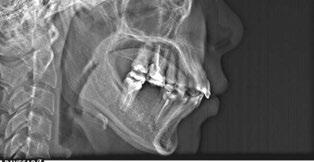

Patient S.T., age 32, presented in the hope of creating a radiant smile and a functional bite. She had been dealing with dental problems all her life. Her X-rays exhibited multiple direct restorations as well as endodontic treatment. Due to the loss of her molars, her teeth had shifted considerably over the years. Her dentist recommended she see us to create a pleasing smile and to rehabilitate her occlusion for future prosthetic treatment (Figure 8).

The patient’s occlusion was super CL I on the left and CL II on the right. Both arches showed slight constriction with lower anterior crowding. Her smile arc was canted, and both midlines were shifted in opposite directions. On cephalometric

analysis, her ANB was 5.84, and IMPA was 102.64, both representative of skeletal Class II with incisor proclination. There were two long-standing extraction sites into which the UR6 and UL6 (partial) had supraerupted. Her thin gingival mucosa posed a challenge in keeping the roots in the bone, so treatment had to be planned correctly and executed gradually to maintain her gingival architecture.